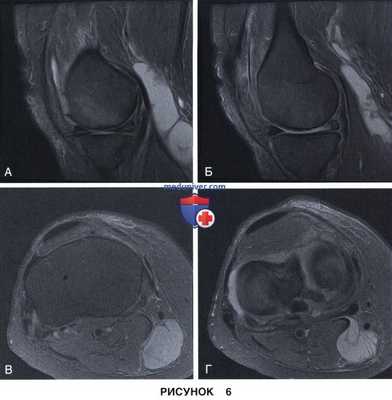

• Неполные разрывы в области верхней или нижней поверхности мениска (рис. 6 и 7)

• ПВУС нередко характеризуется появлением низкоинтенсивных в Т1 - и Т2-режимах узелков в толще синовиальной оболочки, представляющих собой депозиты гемосидерина (рис. 6).